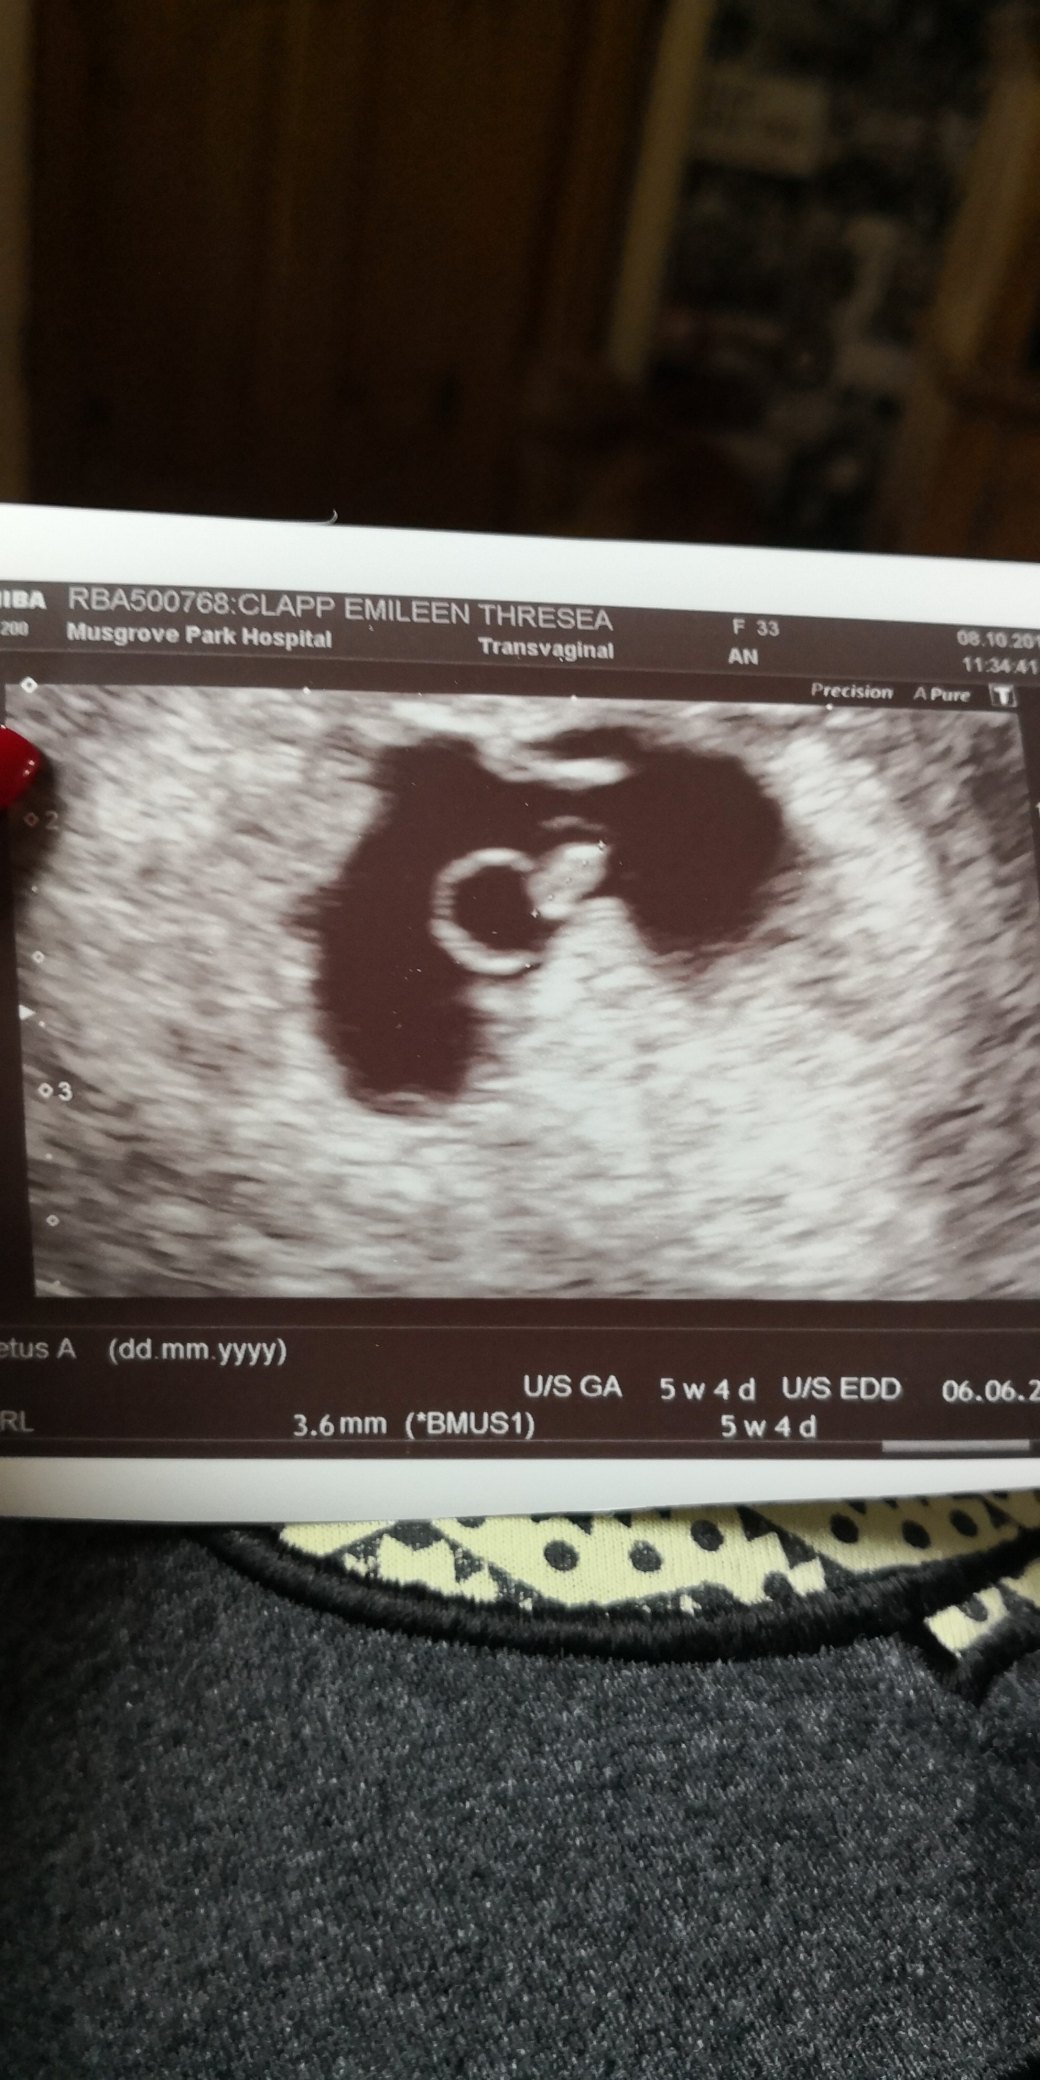

We’re another two weeks into the pregnancy, Paisley had recovered from the hand, foot and mouth, her condition is under control now that we have the right stuff to treat her, I had managed to avoid getting a tempature! All in all things were looking good! We were so excited about the baby, we named the bump Boris, we kept talking about him Infront of the kids, luckily they thought it was someone we know and not our bump name. I had a massive wobble the night before our 6week scan, I told Nathan not to bother coming to the scan, I said they would’t find anything anyway. I don’t know what it was but something just didn’t feel right! My boobs didn’t hurt – I’m sure they hurt at my 6week scans with the girls! I told a friend about the baby, I told her things felt different and I’m scared, she thought the baby was a boy and that’s why it felt different and that I was panicking because the two I lost before the girls. It was a difficult year last year, my eldest should have been 16 on the day we turned 12 weeks and it was 10 years ago that year that I lost the ectopic pregnancy. That thrown in with my poor mental health during my pregnancy with Paisley and all the extra pregnancy hormones = I was a massive scared mess! Anyway we went to our scan feeling calmer than I had the night before, they asked the usual questions, about my previous pregnancies, they asked how the ectopic was treated, I responded “like cancer” and broke down into tears! I gathered myself and got on the bed, the lady was so kind, she told us straight away that the baby was ok and in my womb! I cried again, I was so relieved. She turned the screen and talked us through the scan, we were measuring a bit earlier than we thought we were but that didn’t count at the early scans so we didn’t bother ourselves with it. Then she told us there was a slight abnormality with the shape of the sac, it might be nothing but they needed us to come back in two weeks to check how the baby’s growing and that if I experienced and bleeding I was to go straight in. The baby’s sac was irregular and that may have caused problems meaning the baby wouldn’t grow and we would lose it. We booked our appointment for two weeks time and were told to make a midwife appointment so they could start supporting me with my mental health.

I didn’t take it all in at the time, I went home and had a google and read loads of stories about irregular sacs becoming regular and also lots of stories about it ending in miscarriage! I felt surprisingly calm about it, I have always been told that the sicker you feel during pregnancy, the healthier the baby and my goodness did I feel sick! Trying to hide this pregnancy from the girls was proving very difficult already. I wasn’t going to panic, the baby was in my womb and had a heartbeat…… Or at least that’s what I told myself.